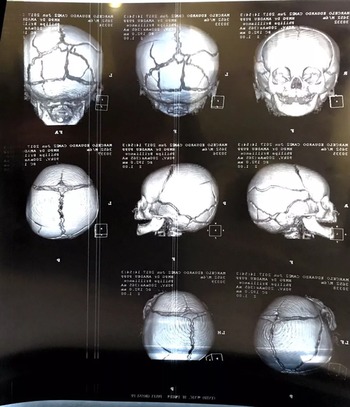

O menino foi levado ao Hospital da Criança em estado grave na semana passada, com várias fraturas no crânio. Na noite desta quinta, ele foi encaminhado para a UTI do Hospital Universitário de Ponta Grossa. Veja a nota dos médicos no final da reportagem.

Segundo a Polícia Civil, o pai foi autuado pelo crime de tortura porque além de múltiplas lesões no crânio, o que indica lesões causadas recentemente, a criança apresentava sinais de mordidas no braço direito, fratura em uma costela e hematomas nas pernas.

- O paciente foi submetido a Tomografia Computadorizada e demais exames indicados. Está sendo acompanhado pelas equipes de Neurocirurgia e de Terapia Intensiva Pediátrica, sendo manejado com tratamento clínico.